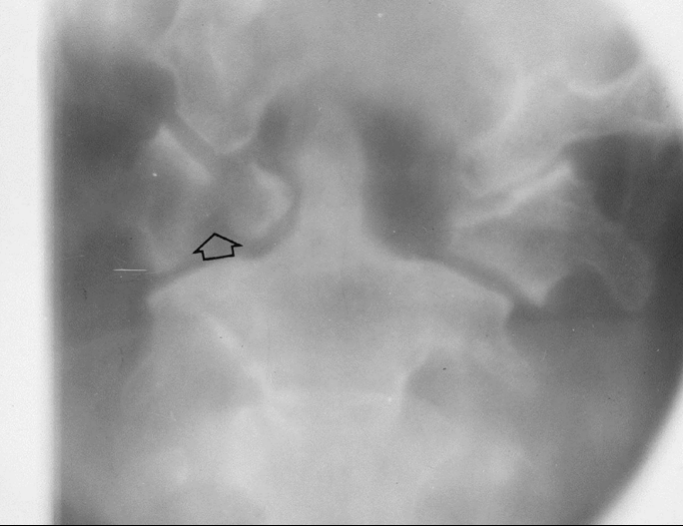

7

Q

What is the diagnosis?

What radiographic sign is present?

A

Intracapsular fracture with effusion/lipohemarthrosis

FBI sign present

8

Sail sign present